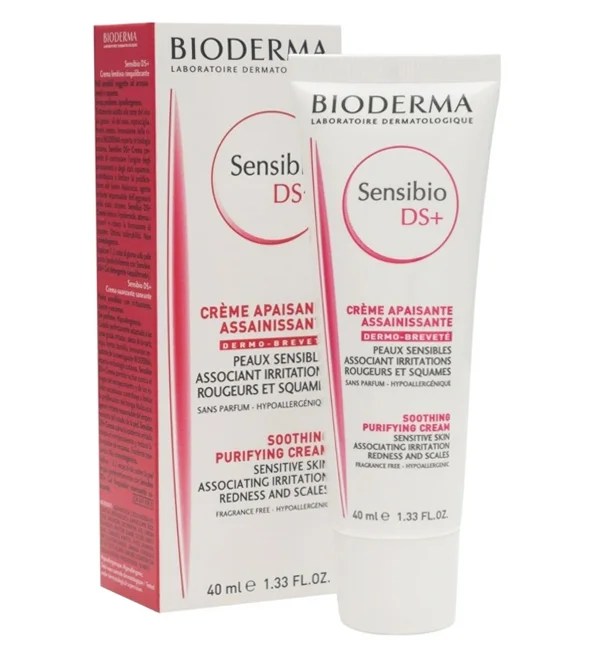

Grâce à une sélection rigoureuse de 650 ingrédients et plus de 40 brevets, Bioderma propose des solutions concrètes et innovantes :- Sensibio (Créaline) : L'icône des peaux sensibles, incluant la célèbre Eau Micellaire Sensibio H2O, pionnière du nettoyage respectueux.